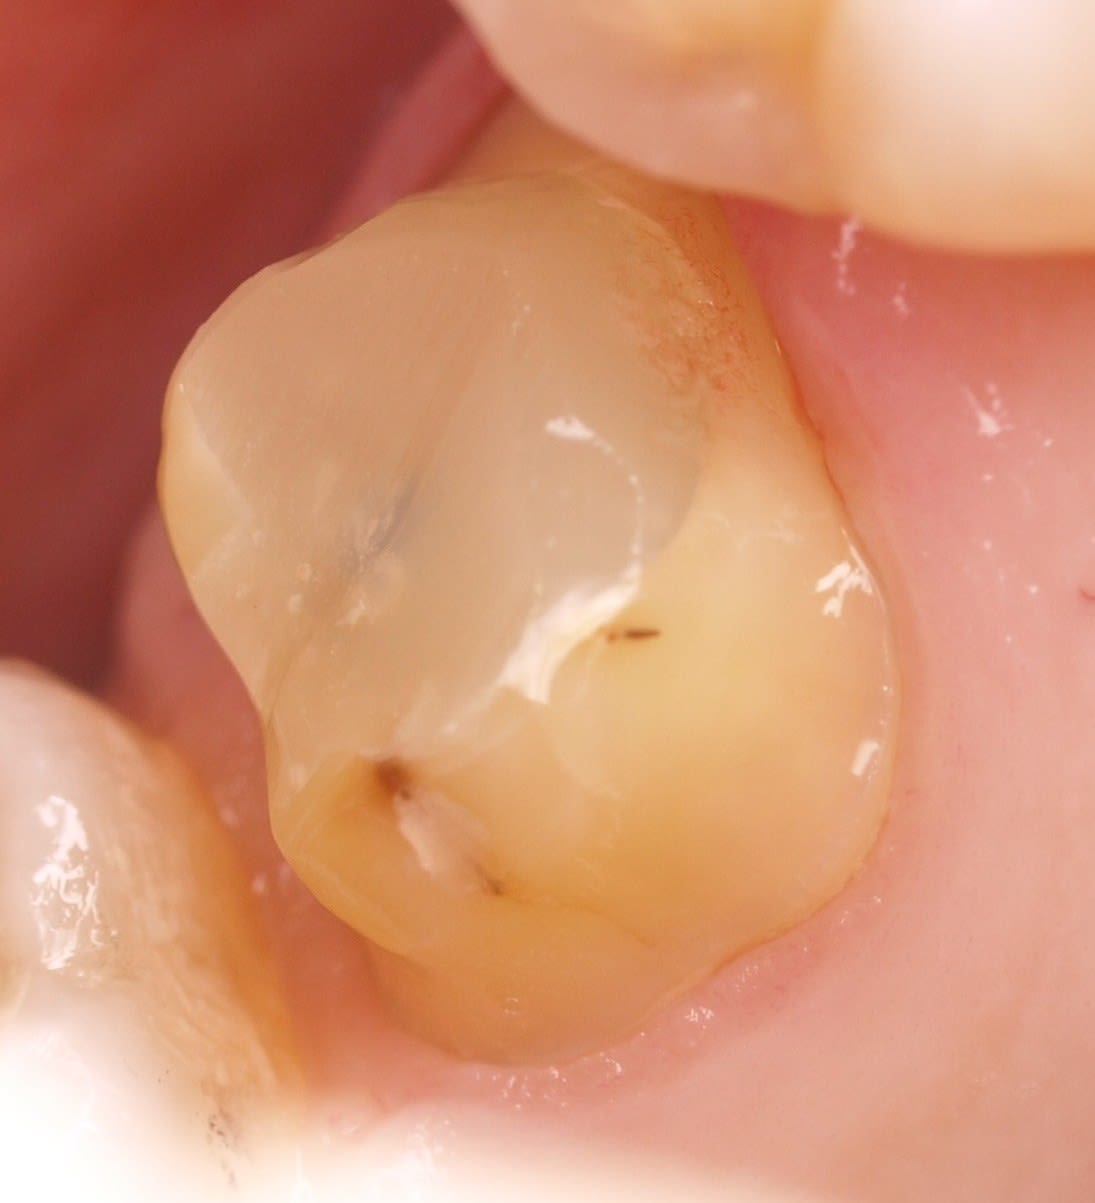

Non c'est pas la meilleure obturation. Ca dépend de son état.

Amalgame fait en décembre 2016. Tu ouvres 2mois après ( sensibilité percussion ++++) et meme pas une goutte de sang.